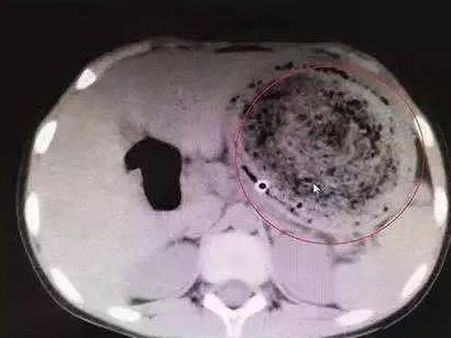

The doctors performed a gastric lavage on her. This procedure was done to empty the contents of her stomach, but doctors were shocked to find that the girl had a huge ball of hair stuck in her stomach.

She Was Operated Immediately